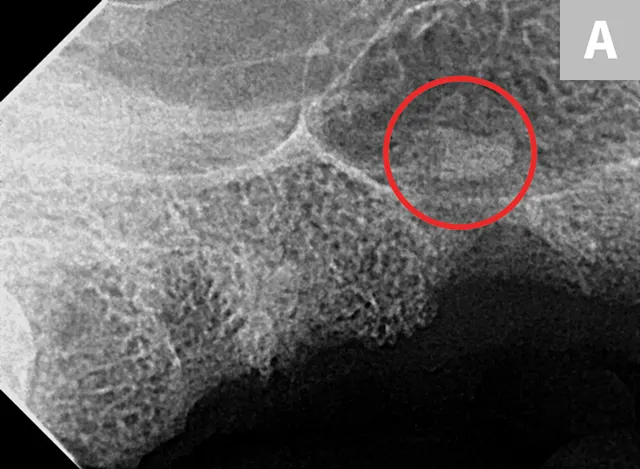

FIGURE 2

Right maxillary premolar tooth root in the nasal cavity (A; circle) and root fragment after removal from the nasal cavity (B)

Root removal from the nasal cavity can be especially difficult because of the large size of the nasal cavity and the potential for tooth root migration. Large mucoperiosteal flaps, bone windows, and suction can aid in the removal process. Avoiding the mandibular neurovascular structures when removing roots from the mandibular canal can be challenging but is crucial, as hemorrhage can occur if structures are punctured.